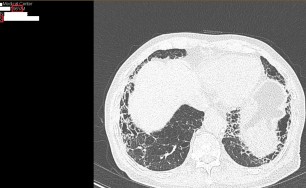

기관지확장증의 CT 사진

​기관지벽의 근육 및 탄력 성분의 파괴로 인해 기관지가 비정상적으로 늘어나 여러가지 문제를 일으키는 질환을 말합니다.

확장된 기관지 내부에는 가래가 고이게 되는데 기관지가 손상되어 있는 상황이므로 잘 빠져나가지 못하게 되고 이로 인해 쉽게 감염되고 그러면서 기관지 벽이 약해집니다. 이렇게 되면 기관지가 쉽게 파괴되고 다시 가래가 증가되는 악순환이 형성됩니다.